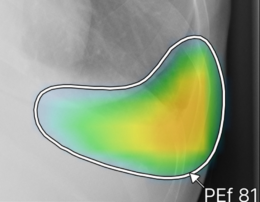

(2)ヒートマップ/輪郭表示機能

異常所見の存在可能性(確信度)を、青から赤へのグラデーションで示すヒートマップ表示について、多くの利用者から好評との声をもらっている。一方、モノクロモニタを利用する一部の読影環境では、淡いヒートマップが確認しにくいという課題があった。新バージョンでは、異常所見の疑われる領域の表示方法として、「ヒートマップ表示」「輪郭表示」「ヒートマップと輪郭の併用表示」の3つの表示パターンが選択可能になった。これにより、各施設の運用環境に応じた最適な表示方法を利用できる。